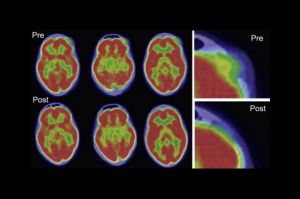

Osýpkami proti rakovine. Vedci našli spôsob, ako bojovať proti zákernej chorobe.

Takmer každý z nás si v detstve prešiel nepríjemnými osýpkami. Napadlo by vám niekedy, že tento vírus, pri ktorom vás všetko svrbí a od hlavy po päty ste celí bodkovaní ako lienka, by niekomu dokázal zachrániť život? Tím vedcov z kliniky Mayo pod vedením Stephena Russela nedávno zverejnil výsledky štúdie, v ktorej jedná veľká dávka modifikovaného vírusu osýpok bola použitá na liečbu rakoviny.